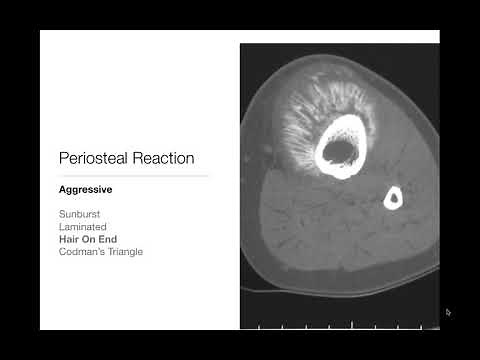

Bone Tumors - Periosteal Reaction - Radiology Basics

Codman Triangle: How It Hints At Bone Cancer